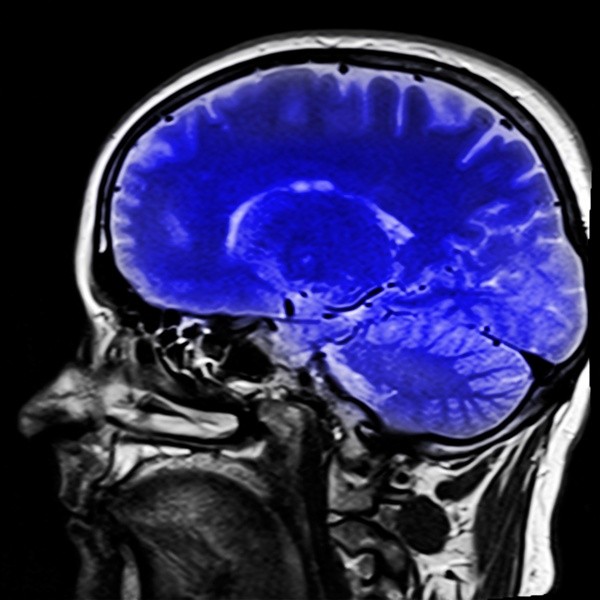

Ученые-нейрофизиологи в Исследовательском институте Скриппса выяснили, что человеческий мозг напрямую влияет на работу жировой ткани в нашем организме. Работу с выводами экспертов публикует журнал Nature.

Авторы проекта отмечают, что жировая ткань млекопитающих содержит значительную долю рецепторов, напрямую связанных с их головным мозгом. В дальнейшем исследование нервных тканей подскажет методы по сжиганию калорий бурого жира.